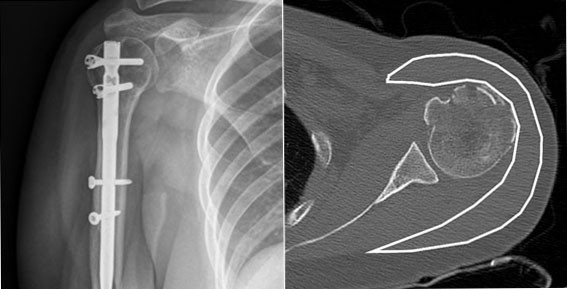

| | ¡è¡è <»çÁøÁ¦°ø=õ¾È¾Æ»êÃæ¹«º´¿ø> | ¨Ï ¿Â¾ç½Å¹® | | õ¾È¡¤¾Æ»êÃæ¹«º´¿ø Á¤Çü¿Ü°ú À¯À缺 ±³¼ö°¡ Ã¥ÀÓÀúÀÚ·Î Âü¿©ÇÑ ¿¬±¸ ³í¹®ÀÌ ±¹Á¦ÇмúÁö¿¡ °ÔÀçµÇ´Â ¼º°ú¸¦ °ÅµÎ¾ú´Ù.

Á¤Çü¿Ü°ú ¼ö¼ú °ü·Ã ÇмúÁöÀÎ ¡°Orthopaedic Research Journal¡±¿¡ °ÔÀçµÈ ¡®Straight proximal humeral nailing can avoiddeltoid atrophy for proximal humeral fracture: A comparison with locking plating¡¯ ³í¹®Àº ¾î±ú »ó¿Ï°ñ °ñÀý Ä¡·á¹ý¿¡ ´ëÇÑ ³í¹®ÀÌ´Ù.

À¯À缺±³¼ö°¡ ¹ßÇ¥ÇÑ ¿¬±¸ °á°ú¿¡ µû¸£¸é ¾î±ú »ó¿Ï°ñ ±ÙÀ§ºÎ °ñÀý ȯÀÚ¿¡°Ô 3¼¼´ë ±Ý¼ÓÁ¤ °íÁ¤¹ýÀ» ½ÃÇàÇÔÀ¸·Î½á »ï°¢±ÙÀ» º¸Á¸ÇÒ ¼ö ÀÖÀ½À» È®ÀÎÇß´Ù.

±âÁ¸ÀÇ °í½ÄÀûÀÎ ±Ý¼ÓÆÇ °íÁ¤¹ý ½ÃÇà ½Ã¿¡´Â ºÒ°¡ÇÇÇÏ°Ô »ï°¢±ÙÀÇ ¼úÈÄ À§ÃàÀÌ ¹ß»ýÇÒ ¼ö ÀÖÀ½À» °í·ÁÇÑ´Ù¸é, 3¼¼´ë ±Ý¼ÓÁ¤ °íÁ¤¹ýÀ¸·Î º¸´Ù ´õ È¿°úÀûÀÎ ¾î±ú »ó¿Ï°ñ °ñÀý Ä¡·á°¡ °¡´ÉÇÏ´Ù´Â Á¡¿¡¼ ÀÇ¹Ì ÀÖ´Â ¿¬±¸·Î Æò°¡ ¹Þ¾Ò´Ù.

| | ¡è¡è ¡ã3¼¼´ë ±Ý¼ÓÁ¤ °íÁ¤¼ú <»çÁøÁ¦°ø=õ¾È¾Æ»êÃæ¹«º´¿ø> | ¨Ï ¿Â¾ç½Å¹® | |

| | ¡è¡è ¡ã¼ö¼ú ÀüÈÄ »ï°¢±ÙÀÇ º¯È ºñ±³ ºÐ¼® <»çÁøÁ¦°ø=õ¾È¾Æ»êÃæ¹«º´¿ø> | ¨Ï ¿Â¾ç½Å¹® | | À¯À缺±³¼ö´Â ¡°¾î±ú »ó¿Ï°ñ °ñÀý ȯÀÚµéÀÇ È¿°úÀûÀÎ Ä¡·á¿¡ À̹ø ¿¬±¸°¡ µµ¿òÀÌ µÇ¾úÀ¸¸é ÇÑ´Ù. ¾ÕÀ¸·Îµµ °ü·Ã ¿¬±¸¸¦ Áö¼ÓÇÏ¿© ȯÀÚµéÀÌ º¸´Ù ºü¸£°Ô °Ç°À» ȸº¹ÇÒ ¼ö ÀÖ´Â »õ·Î¿î Ä¡·á¹æÇâÀ» °è¼ÓÀûÀ¸·Î Á¦½ÃÇÒ ¼ö ÀÖµµ·Ï ³ë·ÂÇϰڴÙ.¡±°í ÀüÇß´Ù.